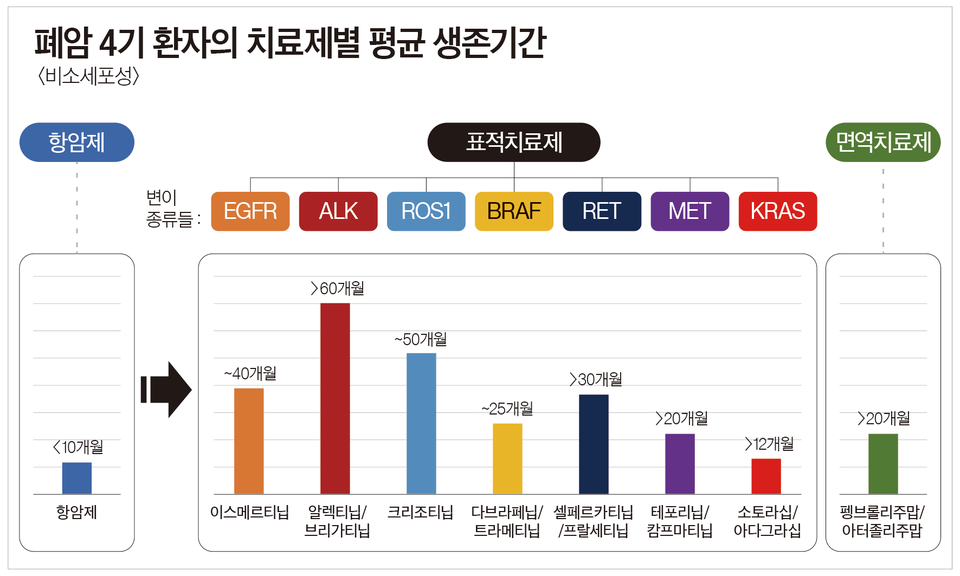

비소세포폐암에서도 유전적 변이를 일으키는 표적항암제를 찾을 수 있다고 한다.

표적항암치료는 정상세포의 유전적 돌연변이로 인해 암세포가 형성되고, 이러한 돌연변이된 세포만을 집중적으로 치료하는 치료법이다.

첫 번째 단계는 유전적 돌연변이에 맞는 약물을 찾는 것이지만, 유전적으로 맞지 않더라도 면역치료나 표적치료제는 사용할 수 있다. (여기서부터는 경제적 측면과 관련이 있습니다.) 이런 표적치료나 치료를 받으면 이전보다 상당한 기간 동안 더 나은 반응을 유지할 수 있다고 합니다. 아무튼 기대됩니다~~!!!!